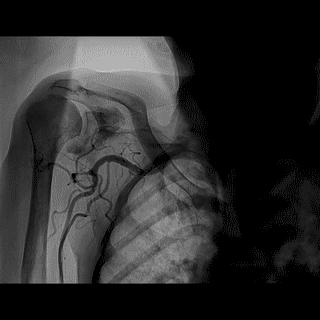

(3)冠状动脉静脉桥血管

首选导管:JR4.0;

其他导管:AL 1.0;AR 1.0

操作:升主动脉造影,寻找静脉桥血管

➢ CASE 3

AL1.0

➢ CASE 4

➢ CASE 5

升主动脉造影未见桥血管显影,原位血管造影也没发现竞争血流迹象,可以确定桥血管已闭塞,必要时可以借助冠脉CTA辅助诊断